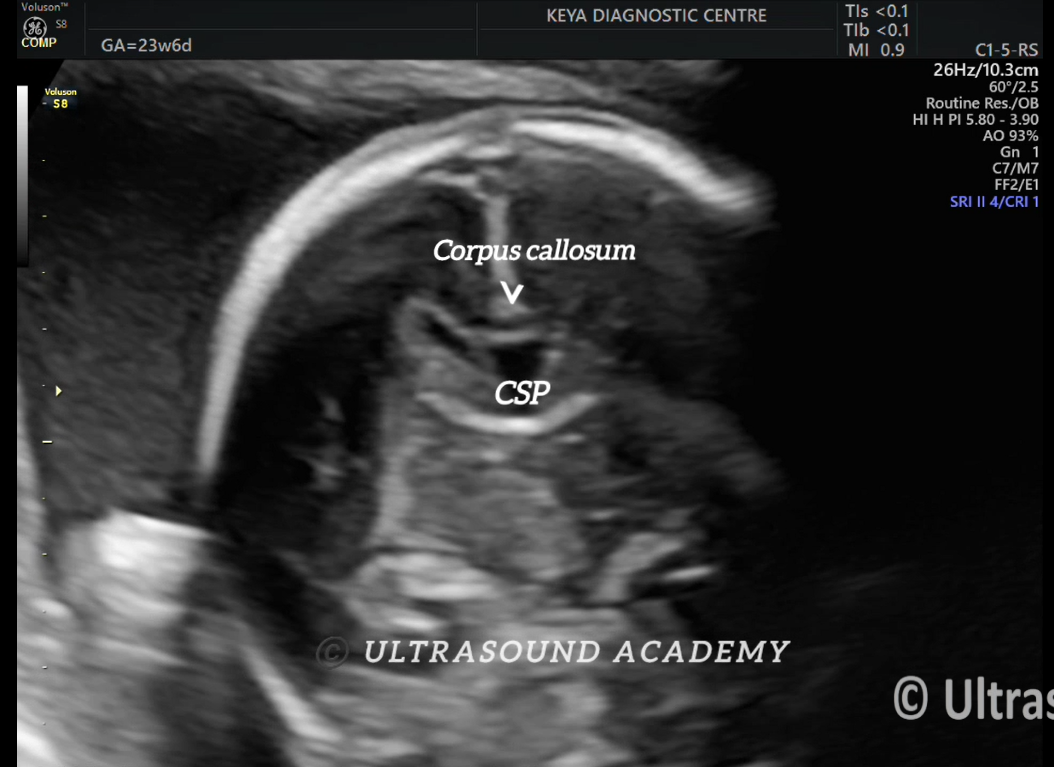

NORMAL CORPUS CALLOSUM AT 23 WEEKS

2D as well as 2D demonstrations of corpus callosum at different weeks of gestation are provided here.

·         The corpus callosum (CC) is the largest commissure connecting the two cerebral hemispheres.

·         It is a broad plate made up of tightly packed axonal fibres crossing from side to side. In the midsagittal section, the corpus callosum extends from the frontal region anteriorly to overlie the tectum or quadrigeminal plate posteriorly.

·         The segments of the CC anterior to posterior are the rostrum, genu, body and splenium. The CC begins to develop at 12 weeks in the region of the genu and progresses posteriorly, forming the body and splenium.